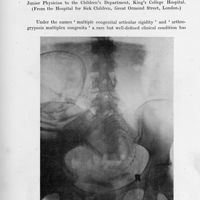

Amyoplasia congenita. (Multiple congenital articular rigidity : Arthrogryposis multiplex congenita)

- Amyoplasia congenita. (Multiple congenital articular rigidity : Arthrogryposis multiplex congenita)

- Archives of Disease in Childhood, Vol. 7, pp. 117-36

- Guérin - Stern (syndrome de)